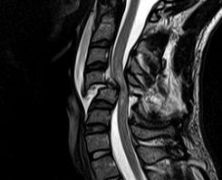

Spinal Cord Injury and how to treat it

More than a quarter of a million Americans live with a spinal cord injury (SCI) [1], which occurs when a physical injury damages or severs spinal cord tissue. This injury can break neural connections from the brain to the limbs that are used to initiate voluntary movement, which in extreme cases results in full or […]